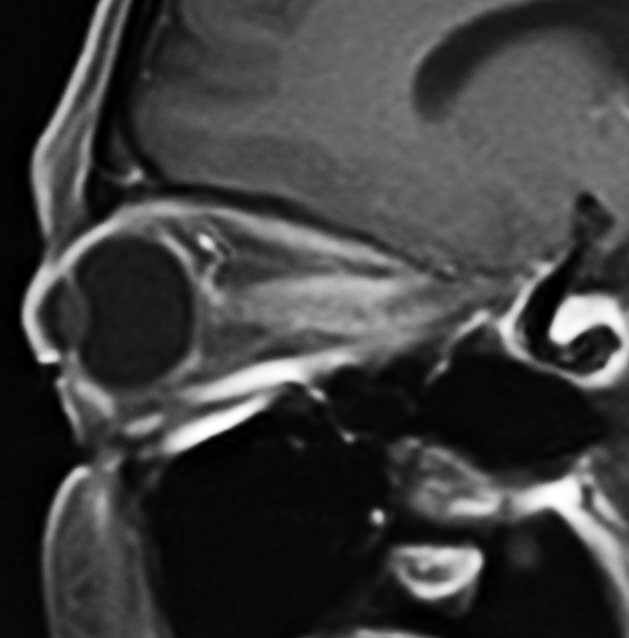

視神経鞘髄膜腫 optic sheath meningioma

眼窩内腫瘍です。視神経を包むし神経鞘から発生して,視神経鞘に沿って進展して増大します。視神経を圧迫してゆっくり症状が出ます。片目の視力が落ちるというのが症状ですが気づかれず発見が遅れることが多いでしょう。眼底検査で,初期には視神経乳頭 optic discの腫れが見られ,視力が悪化していくと視神経萎縮となります。眼底検査で動静脈シャントが見られるのも特徴的で,視力低下と視神経萎縮と併せてHoyt-Spencer triadと言われました。視力がほぼ消失するまで腫瘍が増大すると,眼球が前に押されて,眼球突出 exophhalmus, enophthalmus という症状が出ます。

治療は手術摘出ですが,この腫瘍を摘出するとほぼ確実に片眼の視力を消失します。ですから視力が無くなるまで手術は待機するという考え方が一般的です。数年以上視力があまり低下しないで腫瘍も増大せず経過する患者さんもいます。視力温存目的で治療するなら,視力の良いうちに定位放射線治療を行うべき疾患です。だからといって何でも定位放射線治療をすればよいというものではありません。問題は,視神経管から鞍結節に腫瘍が伸展している例があるということです。ここを放置すると反対側の健常な眼の視力が侵されることになりかねないので慎重に判断します。

右目が暗いという症状で発症して,眼科では視神経乳頭腫脹とわずかな視野欠損だけで発症した患者さんです。3年間観察されましたが,その間には眼底所見も視力 Vd 1.2 も変化がなかったとの眼科からの報告です。そのすぐ後で患者さん本人は,右目が暗くなる回数が増え、視野狭窄があり軽い眼球突出,まわりがぼやけてますが中心は1.0見える状態との訴えで相談を受けました。主治医の先生の方針では経過観察ということで,まだ視力も良いので私もそうした方がよいと同意したのですが,その後半年くらいで視力が手動弁まで低下してしまいました。眼球運動と右眼球を温存するために腫瘍を摘出しました。

鞍結節部から視神経管を伝わり視神経鞘に伸びていた例です。鞍結節部と視神経管での視神経圧迫があったのでそこを除圧するために摘出したのですが,グレード2の髄膜腫で再発しました。下のMRIは,放射線治療 50Gy/25frしてから5年後の画像です。腫瘍は大きくなっていませんし,右の視力はVd 0.5あり,有用視力といえるほどの視野ではありませんが,視野は上の方で残っています。